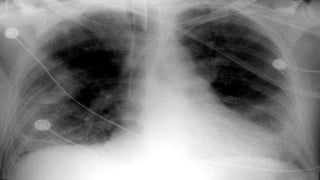

• Atelectasis 1st POD (Auscultation, Chest X-ray, Improve ventilation, Bronchoscopy)

• B/L pulmonary infiltrates, hypoxia with no evidence of CCF